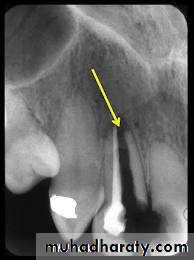

False contraindication of endodontic therapy:- Presence of broken instrument

False contraindication of endodontic therapy:- presence of calcification

- Anatomical difficulties